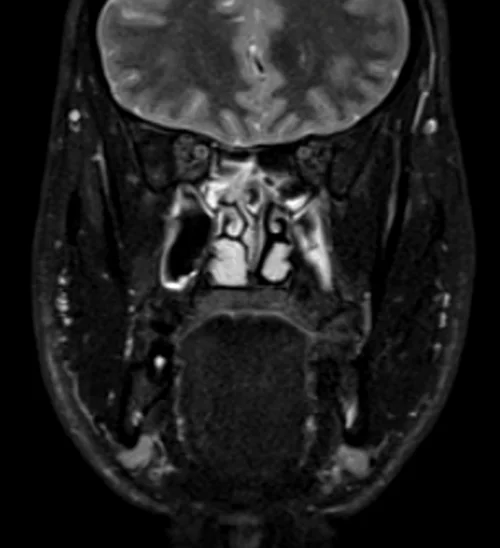

MRI face STIR coronal images